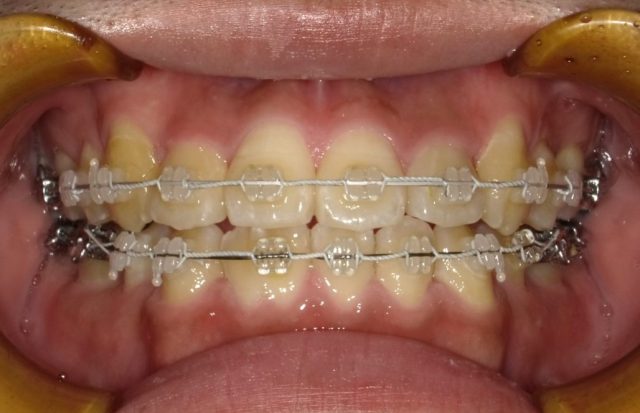

【正面観】

2023年1月